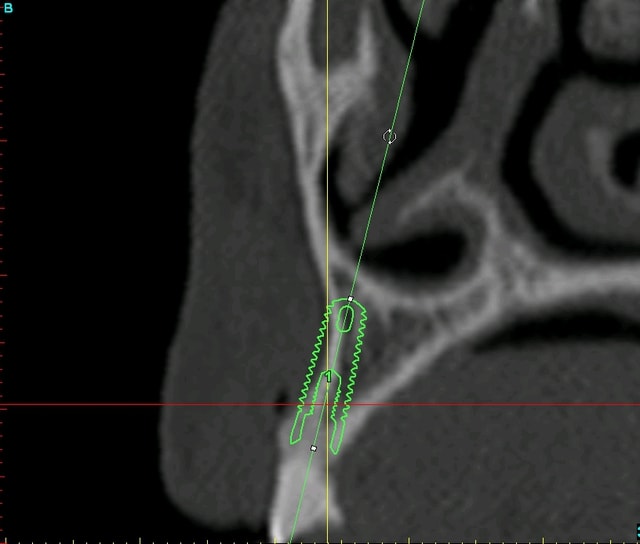

du coup, j'hésite entre 2 type d'interventions pour la pose des implants (mais là çà sera pas avant octobre...)

soit je retire les vis d'ostéosynthèse en faisant une toute petite incision en regard de chaque vis (ce qui me permettra de faire un "mini-lambeau" (séduisant vu que j'aimerai faire une mise en esthétique immédiate...))

soit je ré-ouvre tout en grand et là je reprofile un peu le nonos...

je vous remets les images avant/après pour un comparo...;-)

Planif euc3aq - Eugenol

Plan c8bcsp - Eugenol

tu vas devoir compléter avec une ROG le jour de l'implantation, ce qui n'est pas un problème.

c'est bien ce que je comptais faire growler...

je pense que je vais corriger au piezzo le volume osseux et utiliser les copeaux générés comme biomat...amha y a laaarrrgement ce qu'il faut...;-)